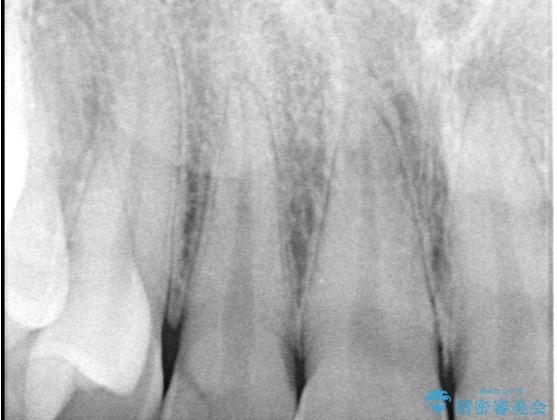

- 主訴:右上の前歯が何しなくても痛い

右上2番の歯に自発痛を認め、症状や歯髄診・レントゲン像から不可逆性歯髄炎と診断し、精密根管治療から歯冠補綴まで行うこととなりました。

初診時に歯髄診断を行い、不可逆性歯髄炎と診断し抜髄から補綴修復までの流れを説明し、精密根管治療、ファイバ-コア築造、オールセラミッククラウン(St)修復を行うこととしました。